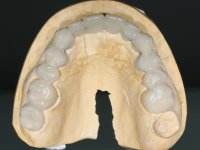

Alginate impressions were made at both arches arcades, accompanied by intermaxillary registration relations and collecting information with facial bow facial bow. In the laboratory, a provisional bridge with 13 elements in autopolymerizable acrylic was built, in which a metallic reinforcement was included. Teeth 1.7 / 1.4 / 1.3 / 2.2 / 2.3 / 2.4 and 2.6 were used as pillars. The metal-ceramic bridge was removed after performing longitudinal cuts with diamond burs. The dental abutments were reprepared and the temporary bridge was relined in the mouth with self-curing acrylic. After confection of the provisional bridge, a gingival epithesis was made using composite resin with gingival tonality in order to function as a mock-up, which allowed the patient to preview the possibility of using gingiva shade ceramics in the final work. This option was approved by the patient. Subsequently, the placement of two implants in the first quadrant was planned and executed. The provisional monoblock was removed for placement of the implants, and after surgery was again cemented provisionally. After the osseointegration period, the impressions were made to the maxilla. In the anterior zone, impregnated gingival retraction cords were used, and in the posterior areas, kaolin paste was used. Implant printing utilized the open tray technique. The printing material used was soft and regular putty addition silicone, both fast-setting. In the laboratory, the model of provisional restorations and the gingiva epithesis mock-up served as orientation for waxing the infrastructure. The plaster work model and the waxing of the infrastructure were placed in a laboratory scanner and yielded a digital work model, in which the scanning of the waxed infrastructure was superimposed. This overlay facilitated the CAD design of the Zr infrastructure. Subsequently, the CAD drawing for a CAM milling process provided the Zr pieces. The infrastructure was pigmented with a pinkish coloration, which favors the subsequent placement of gum shade ceramic. During the modeling of the infrastructure, the need to increase the occlusal wear on tooth 1.4 was detected. This was done in the real working model cast and an acrylic wear control guide was created, which accompanied the proof of the infrastructures. Corrective wear and Zr parts test were performed in mouth. During the test, the color choice of the gum shade ceramic was reassessed. The treatment was finished in the laboratory, and after approval by the patient, was definitively placed in the mouth.